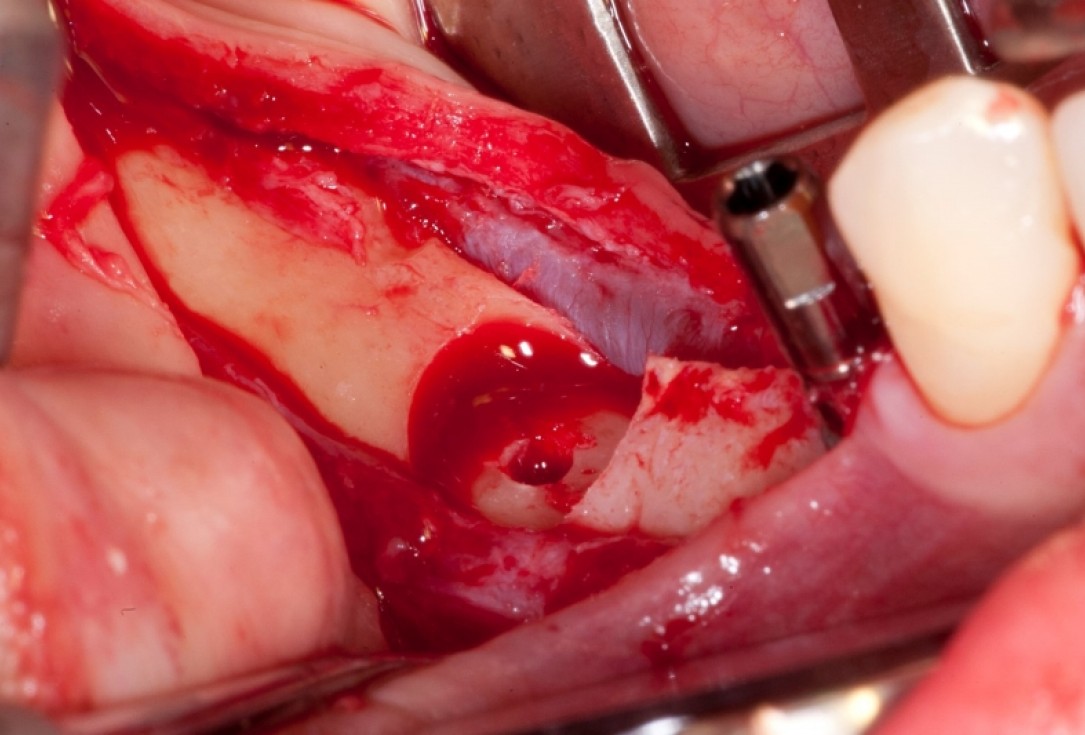

01/18 - Vertical augmentation: Preparation of ring bed in atrophic mandibula (third quadrant)

Vertical augmentation & sinus lift with maxgraft® bonering - Dr. O. Yüksel and Dr. B. Giesenhagen